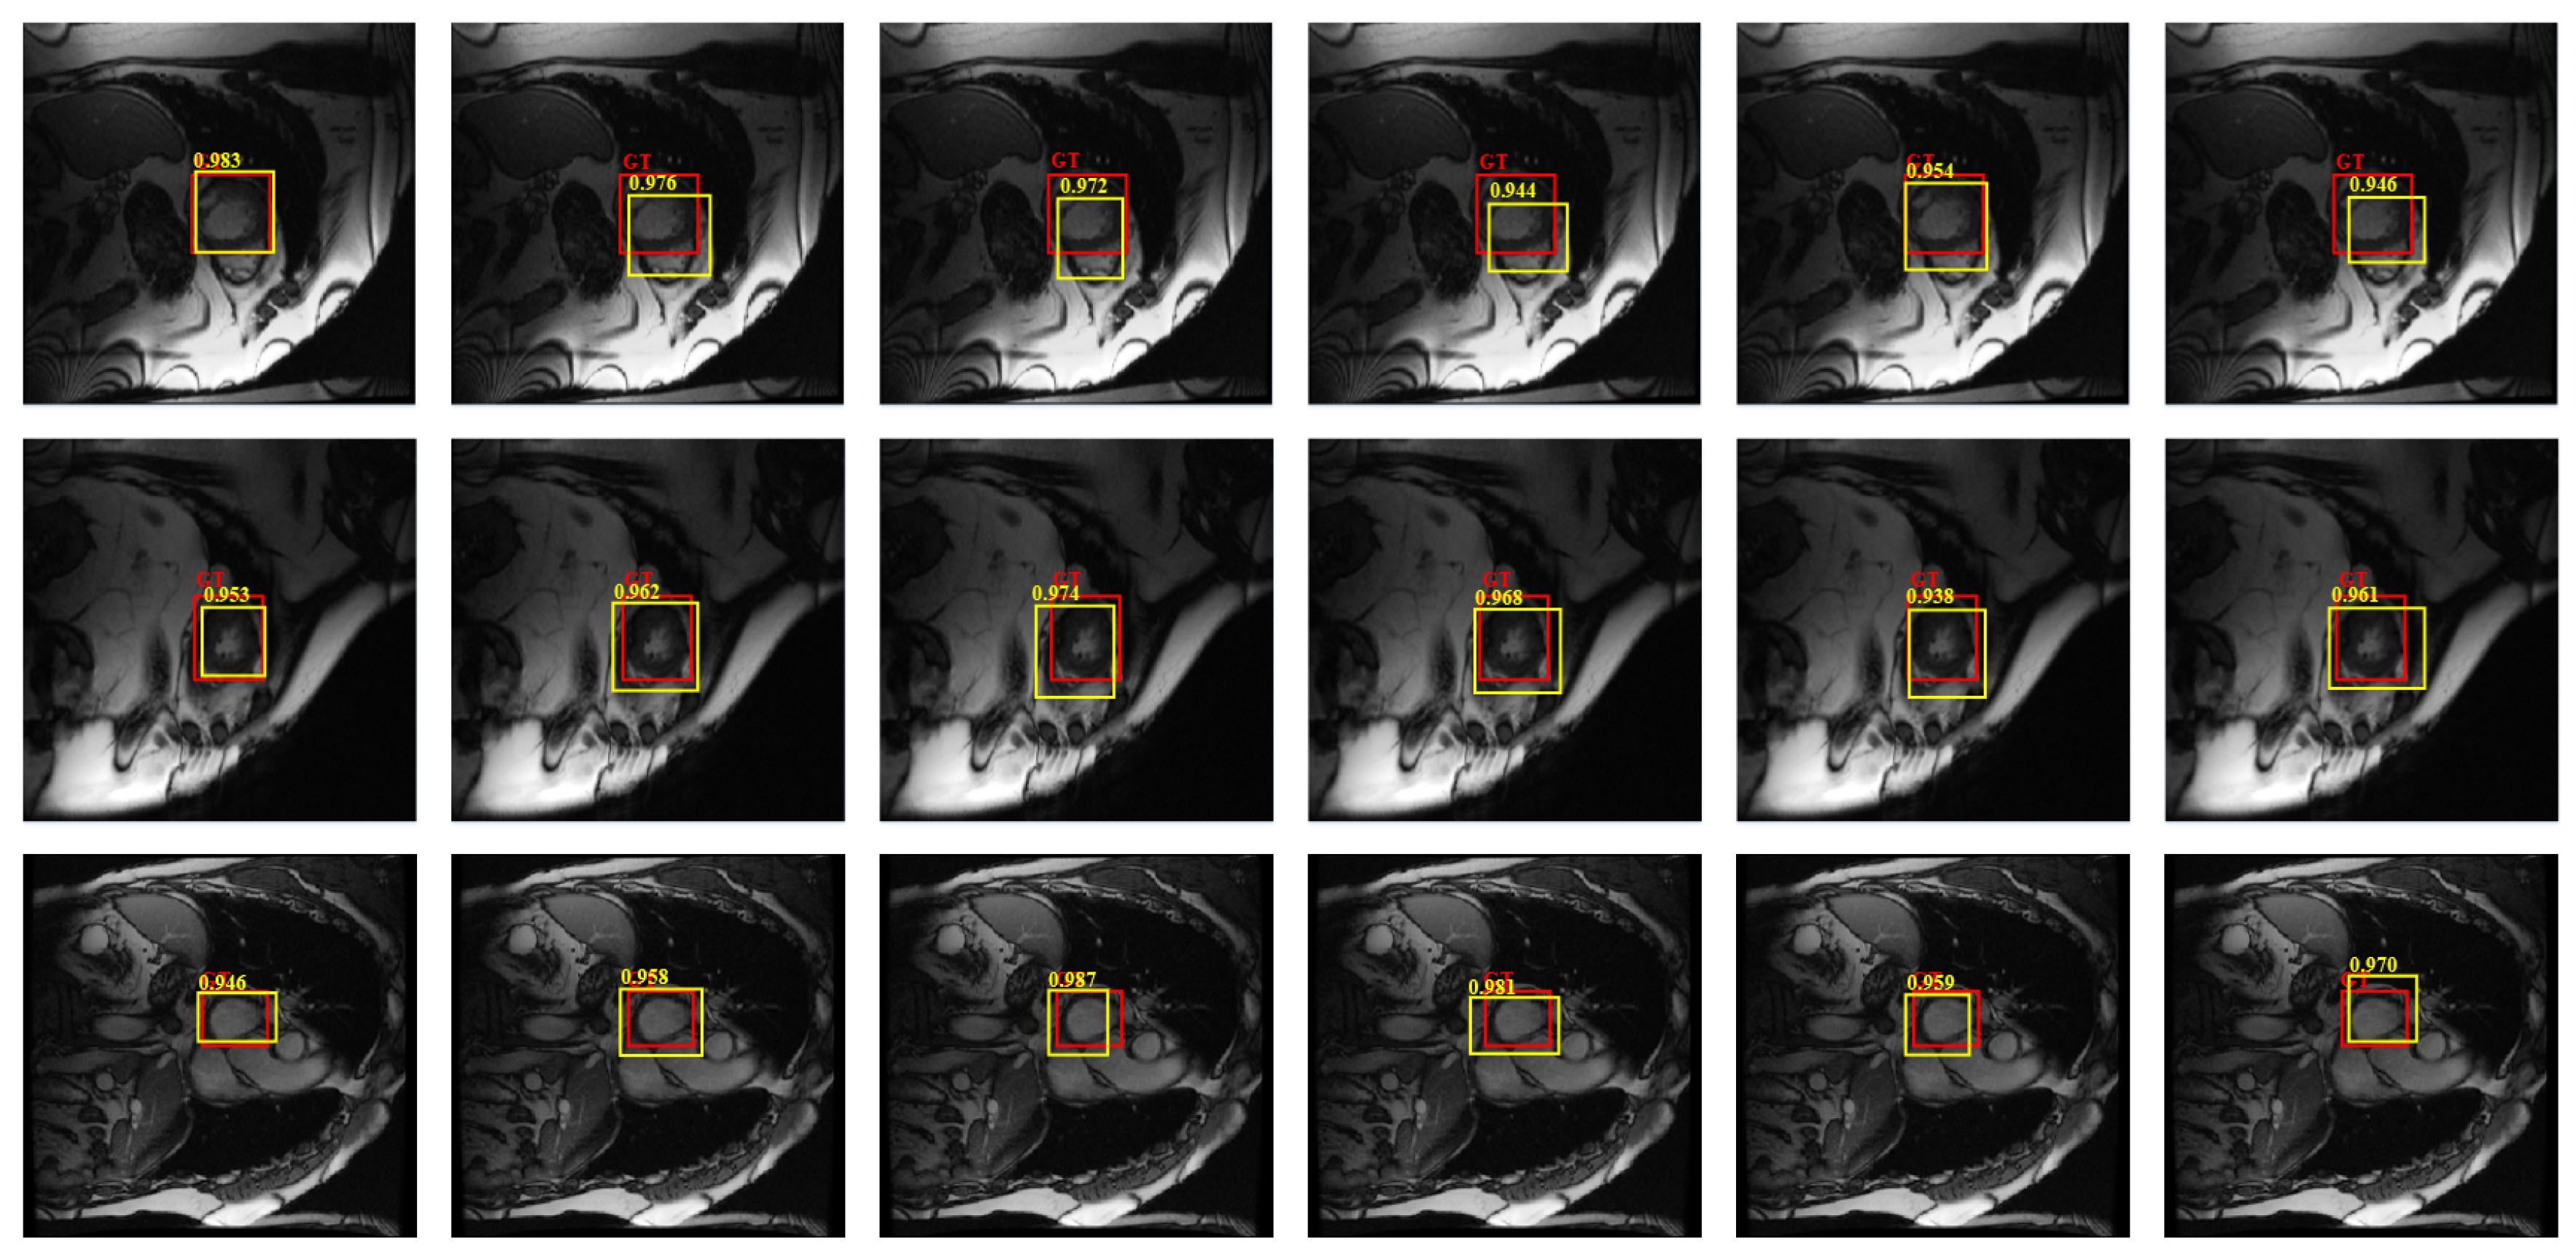

4.2. Validation of the Parts in Our Model

4.4.1. Detection Performance